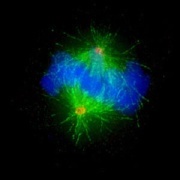

Im menschlichen Organismus finden jede Sekunde mehrere Millionen Zellteilungen (z. B. bei Blut-, Darm-, und Hautzellen) statt: Bei jeder Zellteilung wird der Inhalt der Zelle verdoppelt und auf zwei neue Tochterzellen verteilt. Gleiches geschieht auch mit den Chromosomen, den Trägern der genetischen Information der Zelle (DNA). Hierbei bildet das Zytoskelett aus Mikrotubuli ein feines Netzwerk, die Teilungsspindel, die von den beiden Zentrosomen der Zelle organisiert wird (vgl. Abb. 1).

Das Zentrosom als "Zermonienmeister" der Zellteilung steuert die Teilungsspindel und sorgt dafür, dass die bei der Zellteilung doppelt vorhandenen Chromosomen gleichmäßig auf die neu entstehenden beiden Tochterzellen aufgeteilt und damit auch alle Information und Funktionen der ursprünglichen Zelle "vererbt" werden. Bei Tumorzellen ist diese Aufteilung der Chromosomen und Zentrosomen häufig gestört und es können Zellen mit zu viel oder zu wenig Chromosomen entstehen.

Abb. 1: Immunfluoreszenzmikroskopische Aufnahme einer sich teilenden menschlichen Zelle. Die Chromosomen sind blau, die Mikrotubuli der Teilungsspindel grün und die beiden Zentrosomen gelb/orange eingefärbt. Skala: 10 Mikrometer.